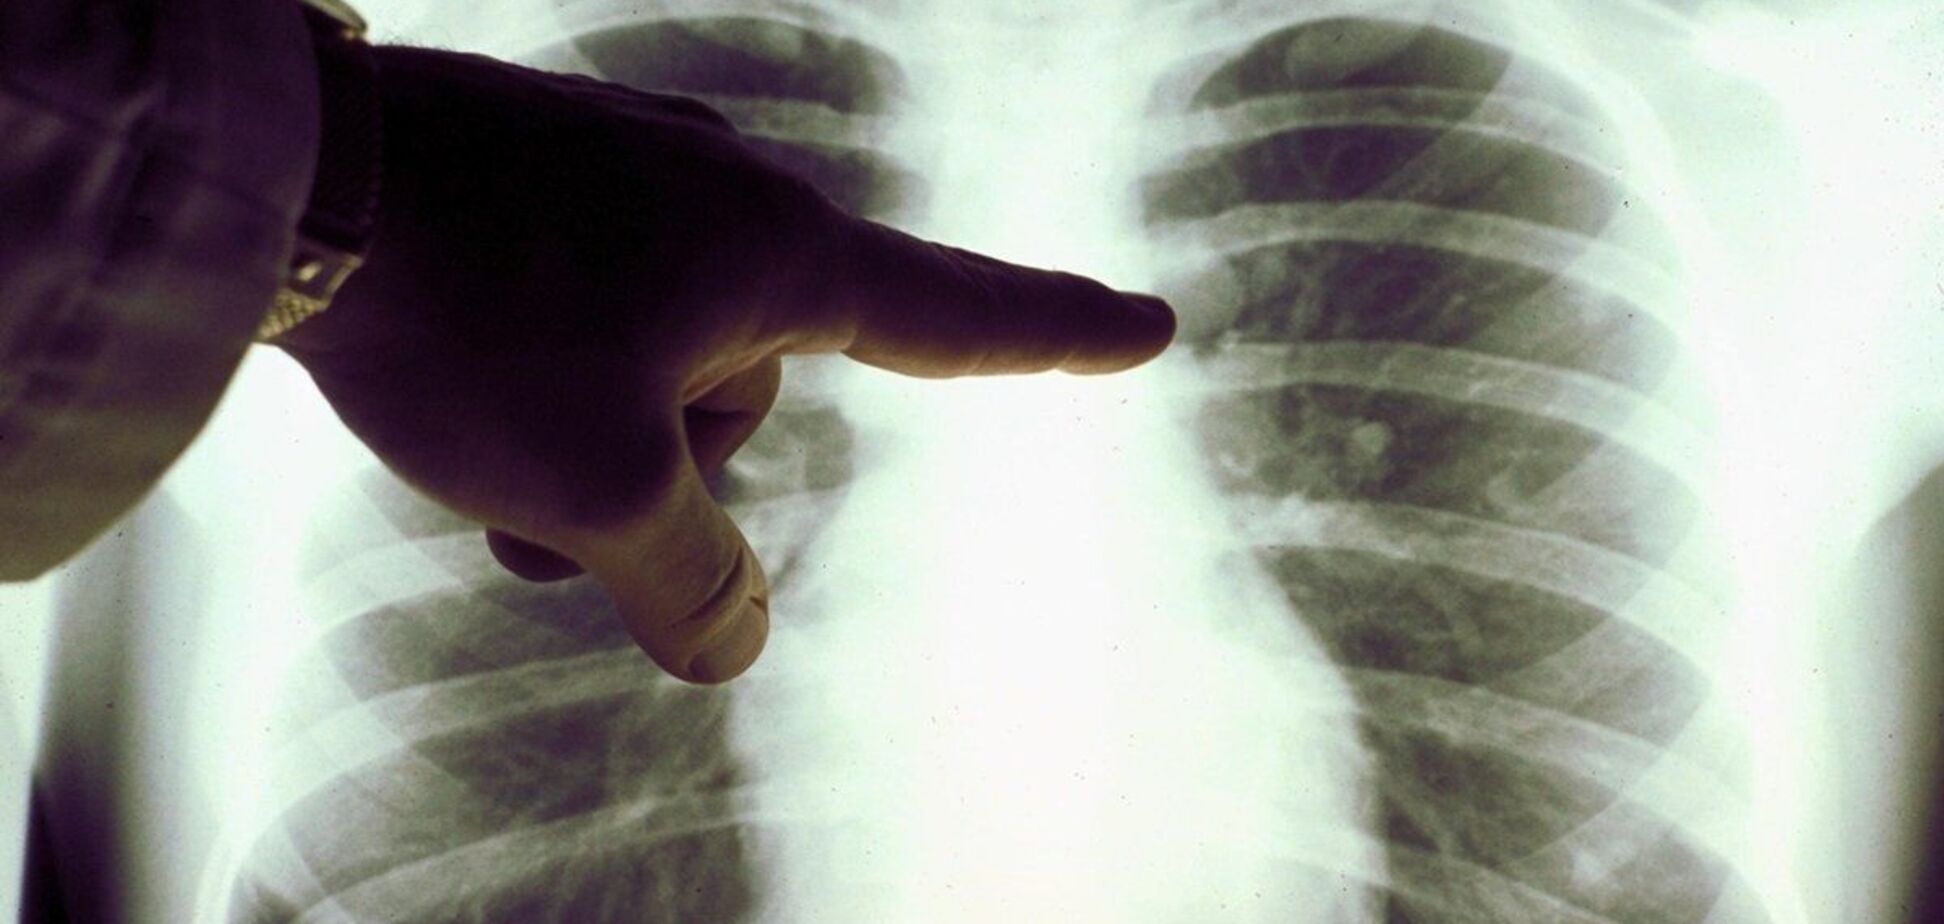

Про це написав на своїй сторінці у Facebook лікар-інфекціоніст Київської міської клінічної лікарні №4 Євген Дубровський. Для підтвердження своїх слів він оприлюднив знімок легень пацієнта та уточнив, що той із першого дня хвороби приймав гропринозин та чотири різновиди антибіотиків.

"На 10 день хвороби така картина. Хтось ще вірить, що антибіотики діють на вірус? Як ще довести, що призначення противірусних категорично заборонено? Що антибіотики шкідливі на ранніх термінах та без показань?! На цьому знімку ми бачимо масивний набряк легень", – написав медик.

За словами Дубровського, цей набряк спричинює неконтрольована гіперімунна відповідь організму на проникнення COVID-19 у легені. А противірусні та антибіотики на ранніх термінах посилюють цю імунну відповідь. Саме тому вони заборонені.